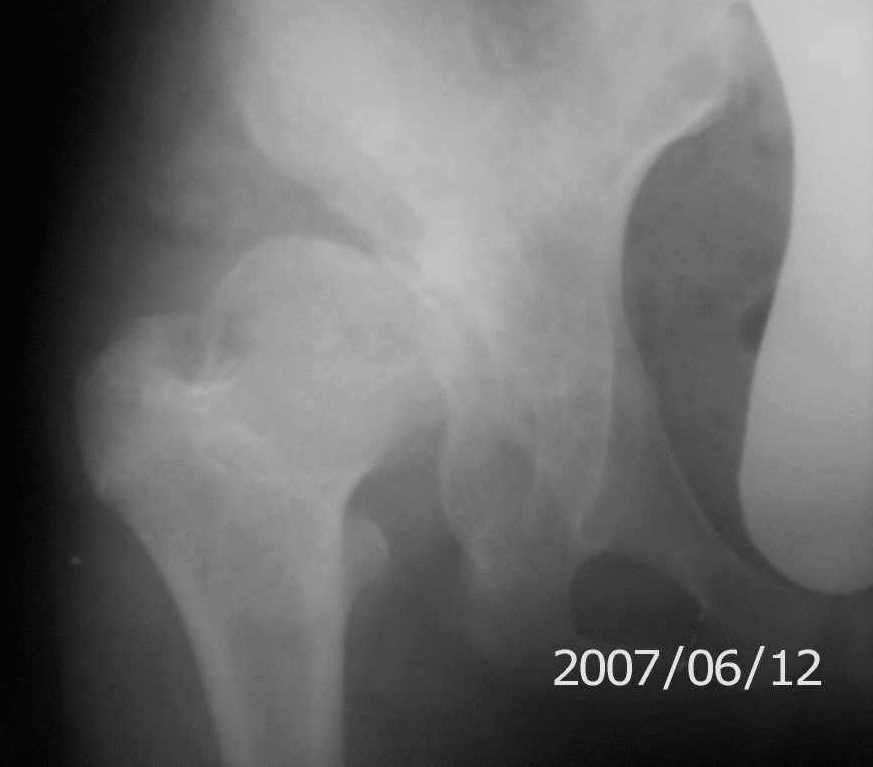

Re: Дисплазия тазобедренного сустава 14 лет

снимки